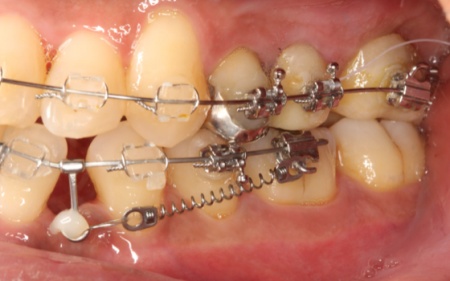

歯を正しい位置に並べるスペースを確保するために、下顎は左右の奥歯(第1小臼歯)を抜き、ワイヤー矯正とクローズドコイルを併用するスピード矯正を、上顎は抜歯せずにワイヤー矯正のみで治療する方法を提案し、同意いただきました。

ワイヤー矯正では、歯の表面にボタン状の四角い器具であるブラケットを接着し、そこにワイヤーを通して歯を動かすマルチブラケット装置を使用します。

治療中の審美性を考慮して、前歯のブラケットは透明で目立ちにくいものを選択しました。

クローズドコイルとは矯正治療用のバネのことで、バネの収縮力を利用し、歯に対して一方向へ一定の力をかけ続けることができます。違和感や痛みがやや出やすいものの、一般的な矯正治療と比べて治療期間の短縮や通院回数の減少が期待できる治療方法です。

まずは、下左右の奥歯2本を抜いてからマルチブラケット装置とクローズドコイルを装着し、歯並びを整えるレベリングを開始します。

レベリングとは、ワイヤーの調整や交換を行いながら歯の傾きを変えたり回転させたりして向きを整え、それぞれの歯を適切な位置へと移動させる工程のことです。

この段階でクローズドコイルを併用すると、歯の移動をより効率的に進めることができます。